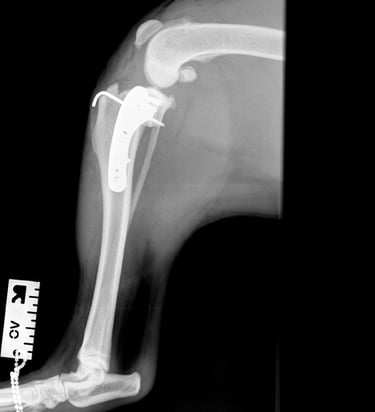

At the first postoperative recheck (day 3), Luna was nearly fully weight-bearing with only mild lameness. The surgical site showed excellent healing and 6 weeks post-op xrays (Figs. 7 and 8) show good ossification of osteotomy line and good position of implants.

Fig. 7

Fig. 8